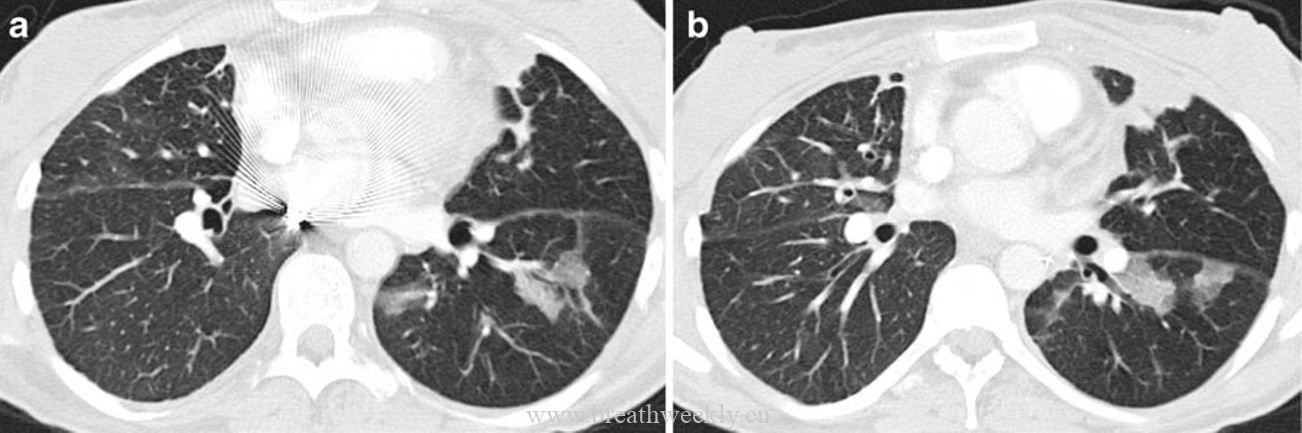

病例9:ARDS

临床资料:67岁女性,全膝关节置换术后发生感染性休克伴ARDS。

影像表现:CT显示双肺磨玻璃影叠加网状影。

病例10:肺水肿

临床资料:83岁男性,急性淋巴细胞性白血病,心功能不全。

影像表现:CT显示斑片状磨玻璃影叠加线状影,小叶内血管扩张呈蜘蛛样。

病例13:机化性肺炎

临床资料:24岁女性,双肺移植术后随访。

影像表现:CT显示斑片状磨玻璃影叠加增厚的小叶间隔。

ARDS是肺水肿的一种形式。CT特征为双肺实变和磨玻璃影,也可见网状和线状影。组织学特征包括肺泡和血管周围水肿,肺泡内富含蛋白的液体填充。进展至结构扭曲和蜂窝肺伴小叶间隔增厚导致线状影。

机化性肺炎是以远端小气道腔内肉芽组织栓子为特征的慢性炎症过程,常延伸至肺泡腔。典型CT表现为散在、不对称的双侧胸膜下和支气管血管周围实变。铺路石征可见但不常见。